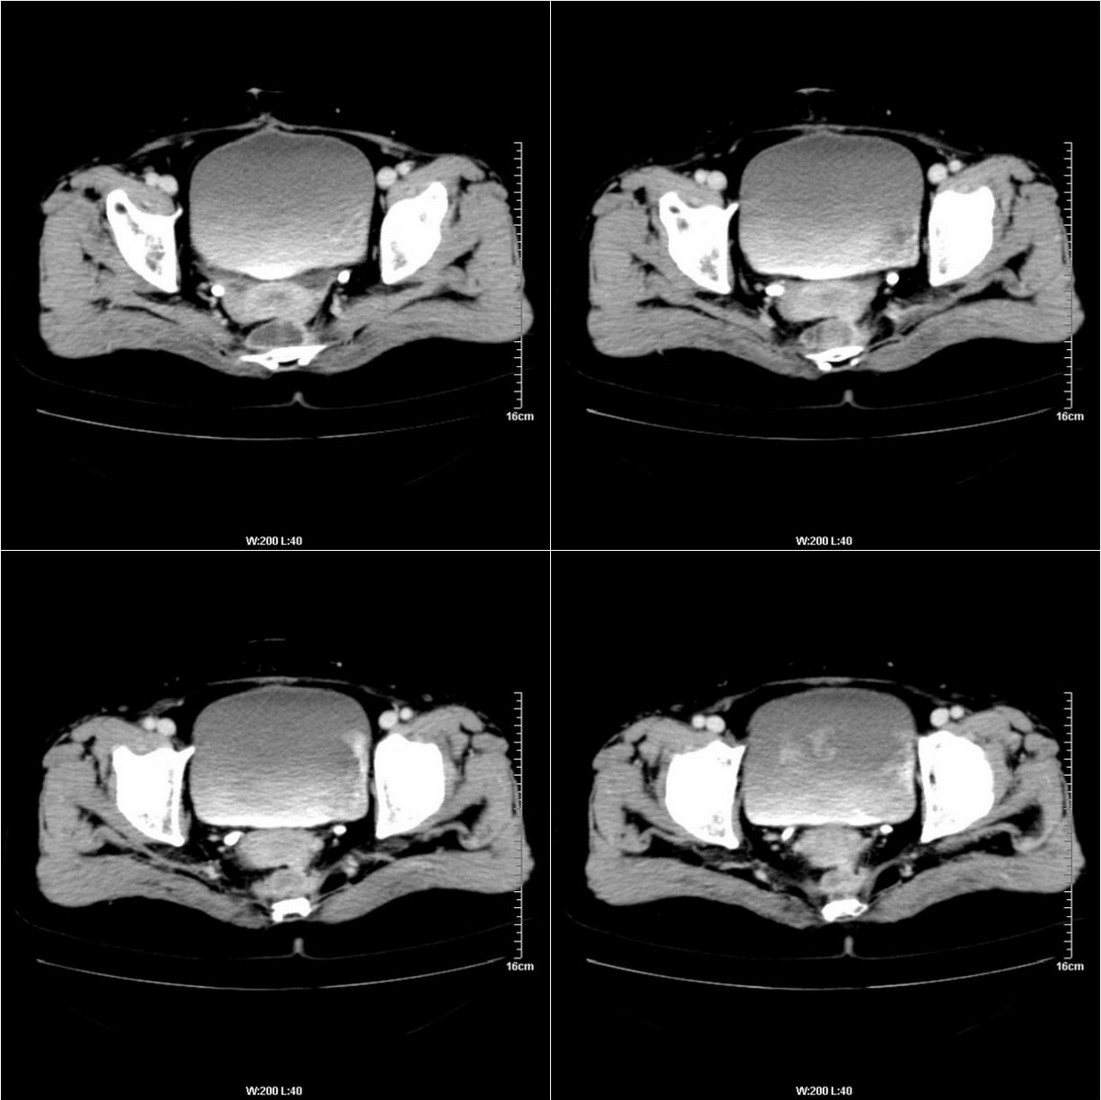

不知道病人的直肠癌手术方式如何,直肠已经全部切除,乙状结肠造瘘于左下腹,肛门应该也没有保留吧?如此,应该是复发了:

病变于肛尾韧带、右侧坐骨肛门窝内并顺右侧肛提肌向右侧闭孔内肌蔓延,骶前软组织内也形成了肿块,麻烦啊!

这个病例还出现了一个有意思的事情:膀胱内在增强的不同时期均有不同形状、位置的高密度出现,并不局限于输尿管开口附近。

是因为尿液中造影剂随输尿管的收缩而排入膀胱内,产生的团片状高密度并进一步弥散而形成的假象吗?渴望哪位老师予以关注并解答,先在此表示感谢了!

典型直肠癌术后骶骨前转移复发.

膀胱壁见索条状软组织密度影伴强化,可考虑炎性肉芽肿样增生改变,常见于放疗后或慢性感染;直肠及周围软组织见肿块,轻度强化,考虑直肠癌术后复发,并侵犯周围组织